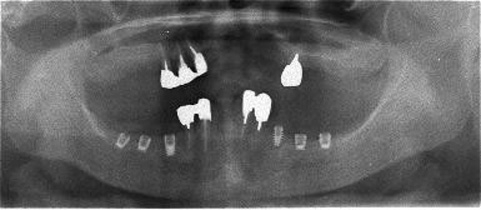

ショートインプラント

術前術前骨の高さが不足している場合、通常のインプラントでは処置が不可能なものが多い。特殊なショートインプラントを用いて可能になる例。 術前 術前CT像術前CT像術前CT像、下歯槽神経が下あごの中央部を走行しているため利用できる骨の高さが少ない。 埋入予定計画埋入予定計画埋入予定計画 術後レントゲン術後レントゲン、ひだりは少し神経をおそれすぎてやや埋入深度が不足、しかしこれでもしっかりと骨と固着した。